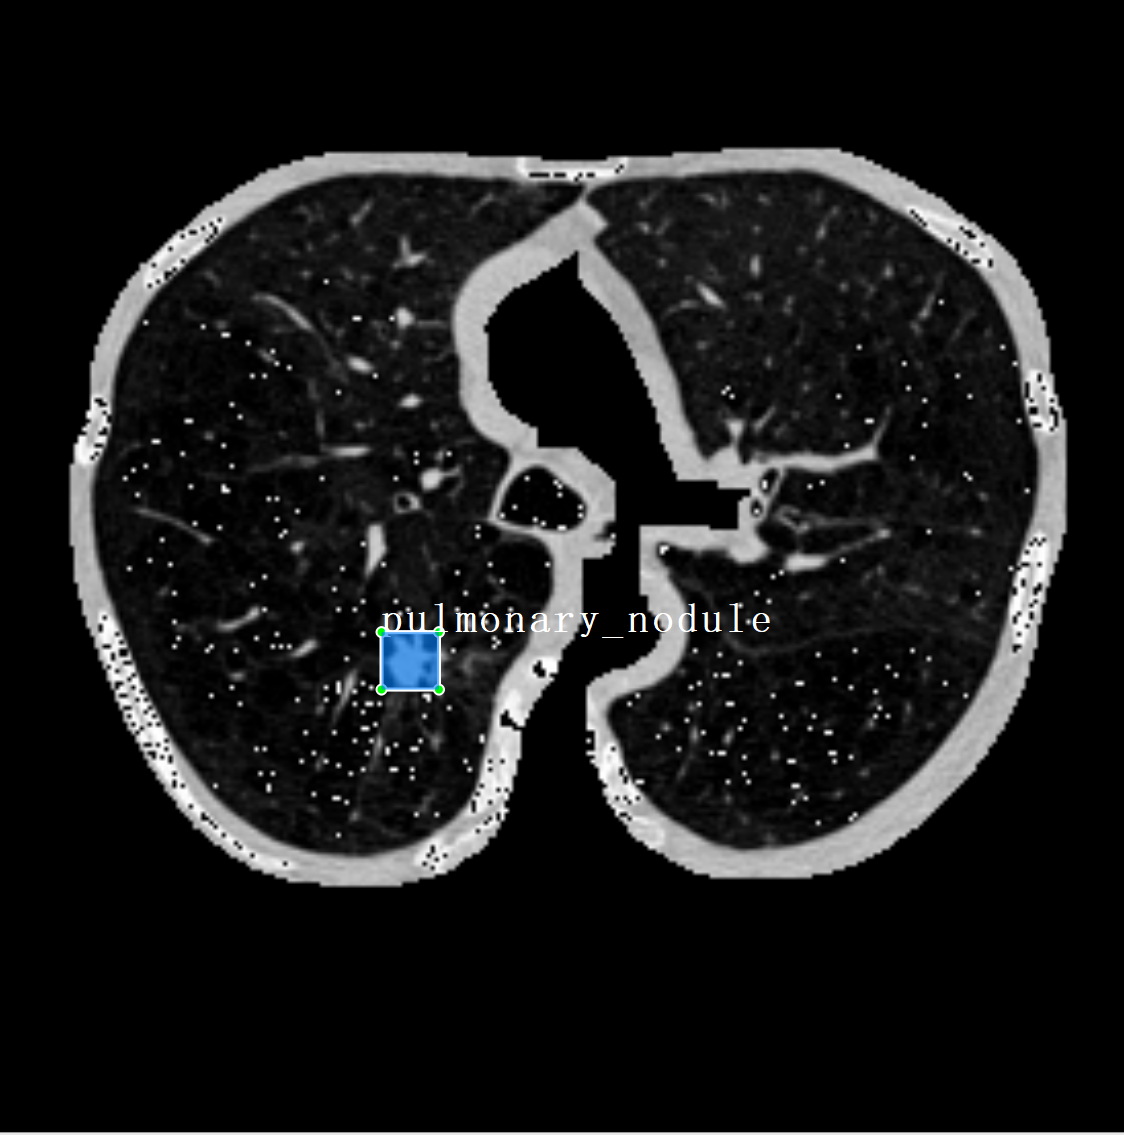

为了更直观地了解处理后的数据效果,下面展示部分转换后的图像切片及其对应的肺结节标注框。每张图像均来源于原始的 CT 切片,经过窗口调节和格式转换处理,最终保存为 .png 格式,并在对应位置绘制结节的边界框。